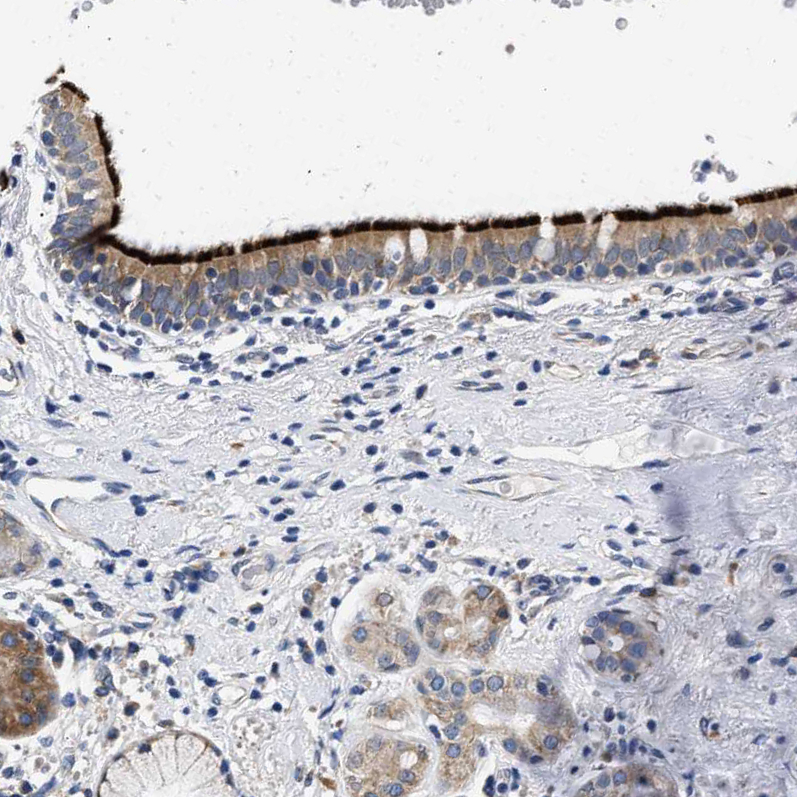

Immunohistochemical staining of human bronchus shows strong positivity in apical membrane in respiratory epithelial cells.